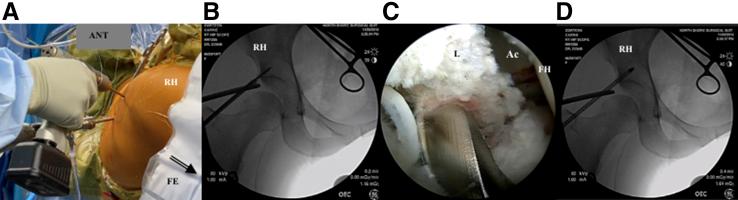

Intraosseous bioplasty (IOBP), has been previously described for arthroscopic-assisted treatment of subchondral bone cysts in the proximal tibia associated with early stages of knee osteoarthritis (OA). This technique entails combining bone marrow aspirate concentrate or concentrated platelet-rich plasma with demineralized bone matrix as a bone substitute before injecting into a subchondral bone defect under fluoroscopic guidance. The principles of IOBP as a procedure that combines core decompression with biologic bone substitute augmentation can be extended to treat subchondral bone marrow lesions such as acetabular and femoral cysts in degenerative hip OA. Intraosseous bioplasty of the hip, in particular the acetabulum, when done using this technique, is a useful alternative that can be beneficial in treating young patients with early hip arthritis to achieve successful outcomes while delaying more invasive procedures. The Technical Note described here presents a step-by-step approach, including tips and pearls for arthroscopic-assisted IOBP with decompression of the subchondral cyst in the acetabulum followed by bone substitute injection under fluoroscopic guidance. We believe this method is a safe and reproducible way to treat subchondral defects in young patients with signs of early osteoarthritis of the hip joint.

摘要

骨内生物成形术(IOBP),此前已被描述用于关节镜辅助治疗与膝关节骨关节炎(OA)早期相关的胫骨近端软骨下骨囊肿。该技术需要在透视引导下将骨髓抽吸浓缩物或富含血小板的浓缩血浆与脱矿骨基质作为骨替代物混合,然后注入软骨下骨缺损处。IOBP作为一种将髓芯减压与生物骨替代物增强相结合的手术方法,其原理可扩展至治疗退行性髋关节OA中的软骨下骨髓病变,如髋臼和股骨囊肿。使用该技术进行髋关节,尤其是髋臼的骨内生物成形术,是一种有用的替代方法,对治疗早期髋关节关节炎的年轻患者有益,可在延迟更具侵入性的手术的同时取得成功结果。此处描述的技术说明介绍了一种逐步方法,包括关节镜辅助IOBP并对髋臼软骨下囊肿进行减压,随后在透视引导下注射骨替代物的技巧和要点。我们认为该方法是治疗有早期髋关节骨关节炎迹象的年轻患者软骨下缺损的一种安全且可重复的方法。